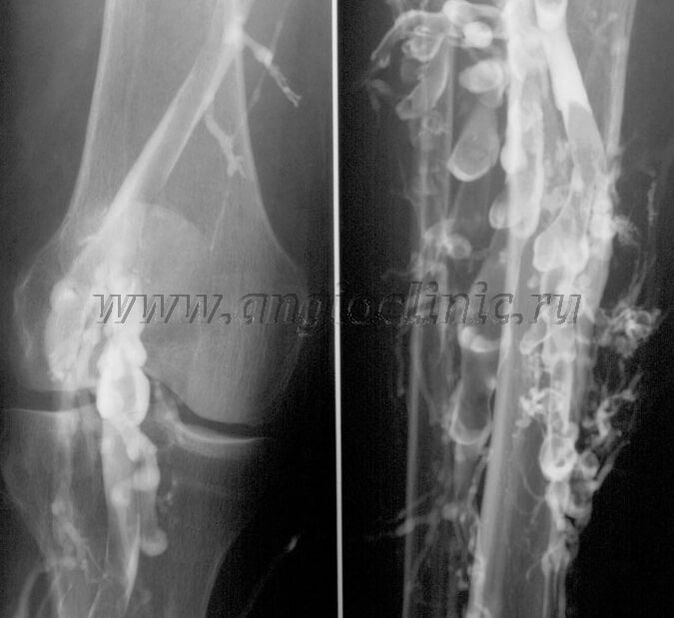

Venografía de contraste

Habitualmente, la ecografía es suficiente para un diagnóstico completo de patología venosa, pero en algunos casos es necesario estudiar la relación entre el estado del sistema venoso profundo y superficial, especialmente en caso de recaídas de varices y varices secundarias.

Exploración por ultrasonido

Para resolver estos problemas se utiliza el examen radiográfico con contraste. Se perforan las venas safenas y se administra contraste. El movimiento del contraste se observa en el monitor del aparato de rayos X y se realizan todas las pruebas y proyecciones necesarias. Actualmente, la venografía para las venas varicosas se utiliza muy raramente.